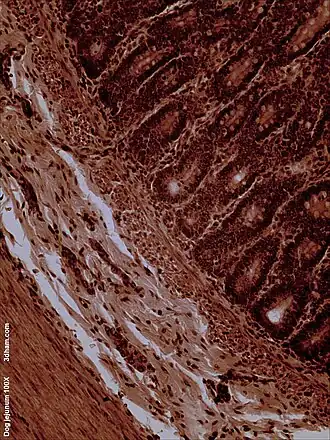

La superficie interna del yeyuno, formada por una membrana mucosa, está cubierta en las proyecciones llamadas vellosidades, que aumentan la superficie de tejidos disponibles para absorber los nutrientes de los alimentos previamente digeridos por el estómago. Las células anales epiteliales que recubren estas vellosidades tienen un número aún mayor de microvellosidades. Son las vellosidades y las microvellosidades las que permiten que en una pequeña porción de tubo digestivo, se absorba una gran cantidad de nutrientes. El transporte de nutrientes a través de las células epiteliales a través del yeyuno y el íleon incluye el transporte pasivo de la fructosa, el azúcar y el transporte activo de aminoácidos, péptidos pequeños, vitaminas, y la mayoría de la glucosa. El ácido fólico, metabolito esencial del ciclo celular, es absorbido principalmente a este nivel del intestino delgado. Las vellosidades en el yeyuno son mucho más largas que en el duodeno o el íleon.

Fosa yeyunoduodenal. -